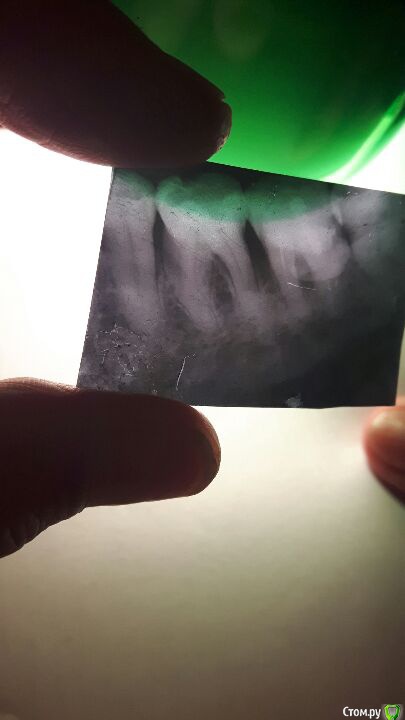

Ptizchen Опубликовано 30 октября, 2017 Поделиться Опубликовано 30 октября, 2017 (изменено) Уважаемые стоматологи,хочу попросить совета. У моей мамы в августе отломился кусок внутренней стенка и на семерке а в конце августа ей его запломбировали. Сейчас у нее воспалилась десна и обнаружили свищ. Ей вскрыли нагноение и сказали что надо рвать. Нам рвать очень страшно и конечно надеемся спасти зуб. Она живет в г. Донецке. Посмотрите пожалуйста на снимок. Можно ли еще попытаться его спасти? Заранее благодарна!с уважением, Мария Изменено 30 октября, 2017 пользователем Ptizchen Ссылка на комментарий

shishok Опубликовано 30 октября, 2017 Поделиться Опубликовано 30 октября, 2017 (изменено) Снимок очень плохого качества.И хорошо бы в полости рта посмотреть(особенно глубину скола стенки). Изменено 30 октября, 2017 пользователем shishok 1 Ссылка на комментарий

DrNice Опубликовано 30 октября, 2017 Поделиться Опубликовано 30 октября, 2017 Качество снимка оставляет желать лучшего... Нужен очный осмотр. 1 Ссылка на комментарий

red_butler Опубликовано 31 октября, 2017 Поделиться Опубликовано 31 октября, 2017 Сделайте новый снимок на визиографе и фото во рту Ссылка на комментарий